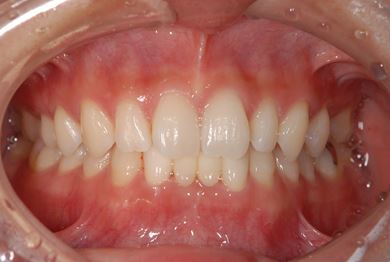

| 主訴 | 下前歯の色が気になるので、ホワイトニングかセラミック治療できれいにしたい。(下前歯2本は乳歯でした) | ||||||||||||||||||||||||||||||||

| 治療方針 | 下顎前歯、乳歯を抜歯し、セラミック治療にて審美的回復を行う。 | ||||||||||||||||||||||||||||||||

| 治療内容 | エンプレスジルコニアフレームオールセラミッククラウンブリッジ4本 | ||||||||||||||||||||||||||||||||

| 総治療費 | 723,450円 | ||||||||||||||||||||||||||||||||

| 治療期間 | 2ヶ月 |